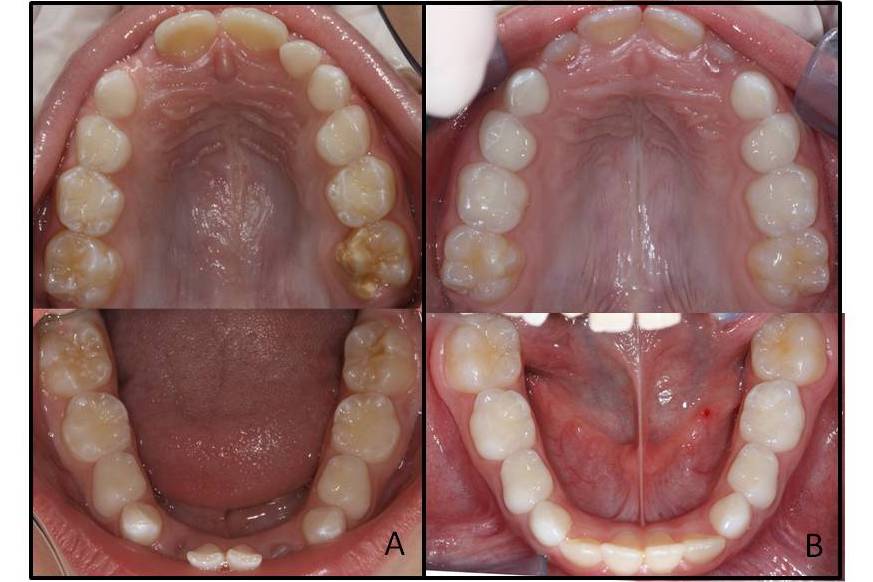

Molar-incisor hypomineralisation is a qualitative defect of dental tissue of systemic origin affecting one or more permanent first molars and sometimes the permanent incisors as well. There are still no conclusive data on the aetiology of this hypomineralisation, however, systemic factors such as respiratory diseases and prenatal and perinatal complications are regarded as possible causes. The objective is to present three clinical cases of twins, one Monozygotic Twins , and two Dizygotic Twins with molar-incisor hypomineralisation, besides showing evidence of its manifestation as well as clinical the characteristics and aetiological factors involved. The clinical findings involving twins show that ameloblasts are specifically affected in their developmental phase, which includes a number of factors although prenatal and perinatal complications not decisive in the development of molar-incisor hypomineralization and suggest a possible genetic susceptibility to the disease. Prospective observational studies using a population sample containing data on the last three months of gestation to the eruption of permanent teeth are needed to confirm the cause-effect relationships.